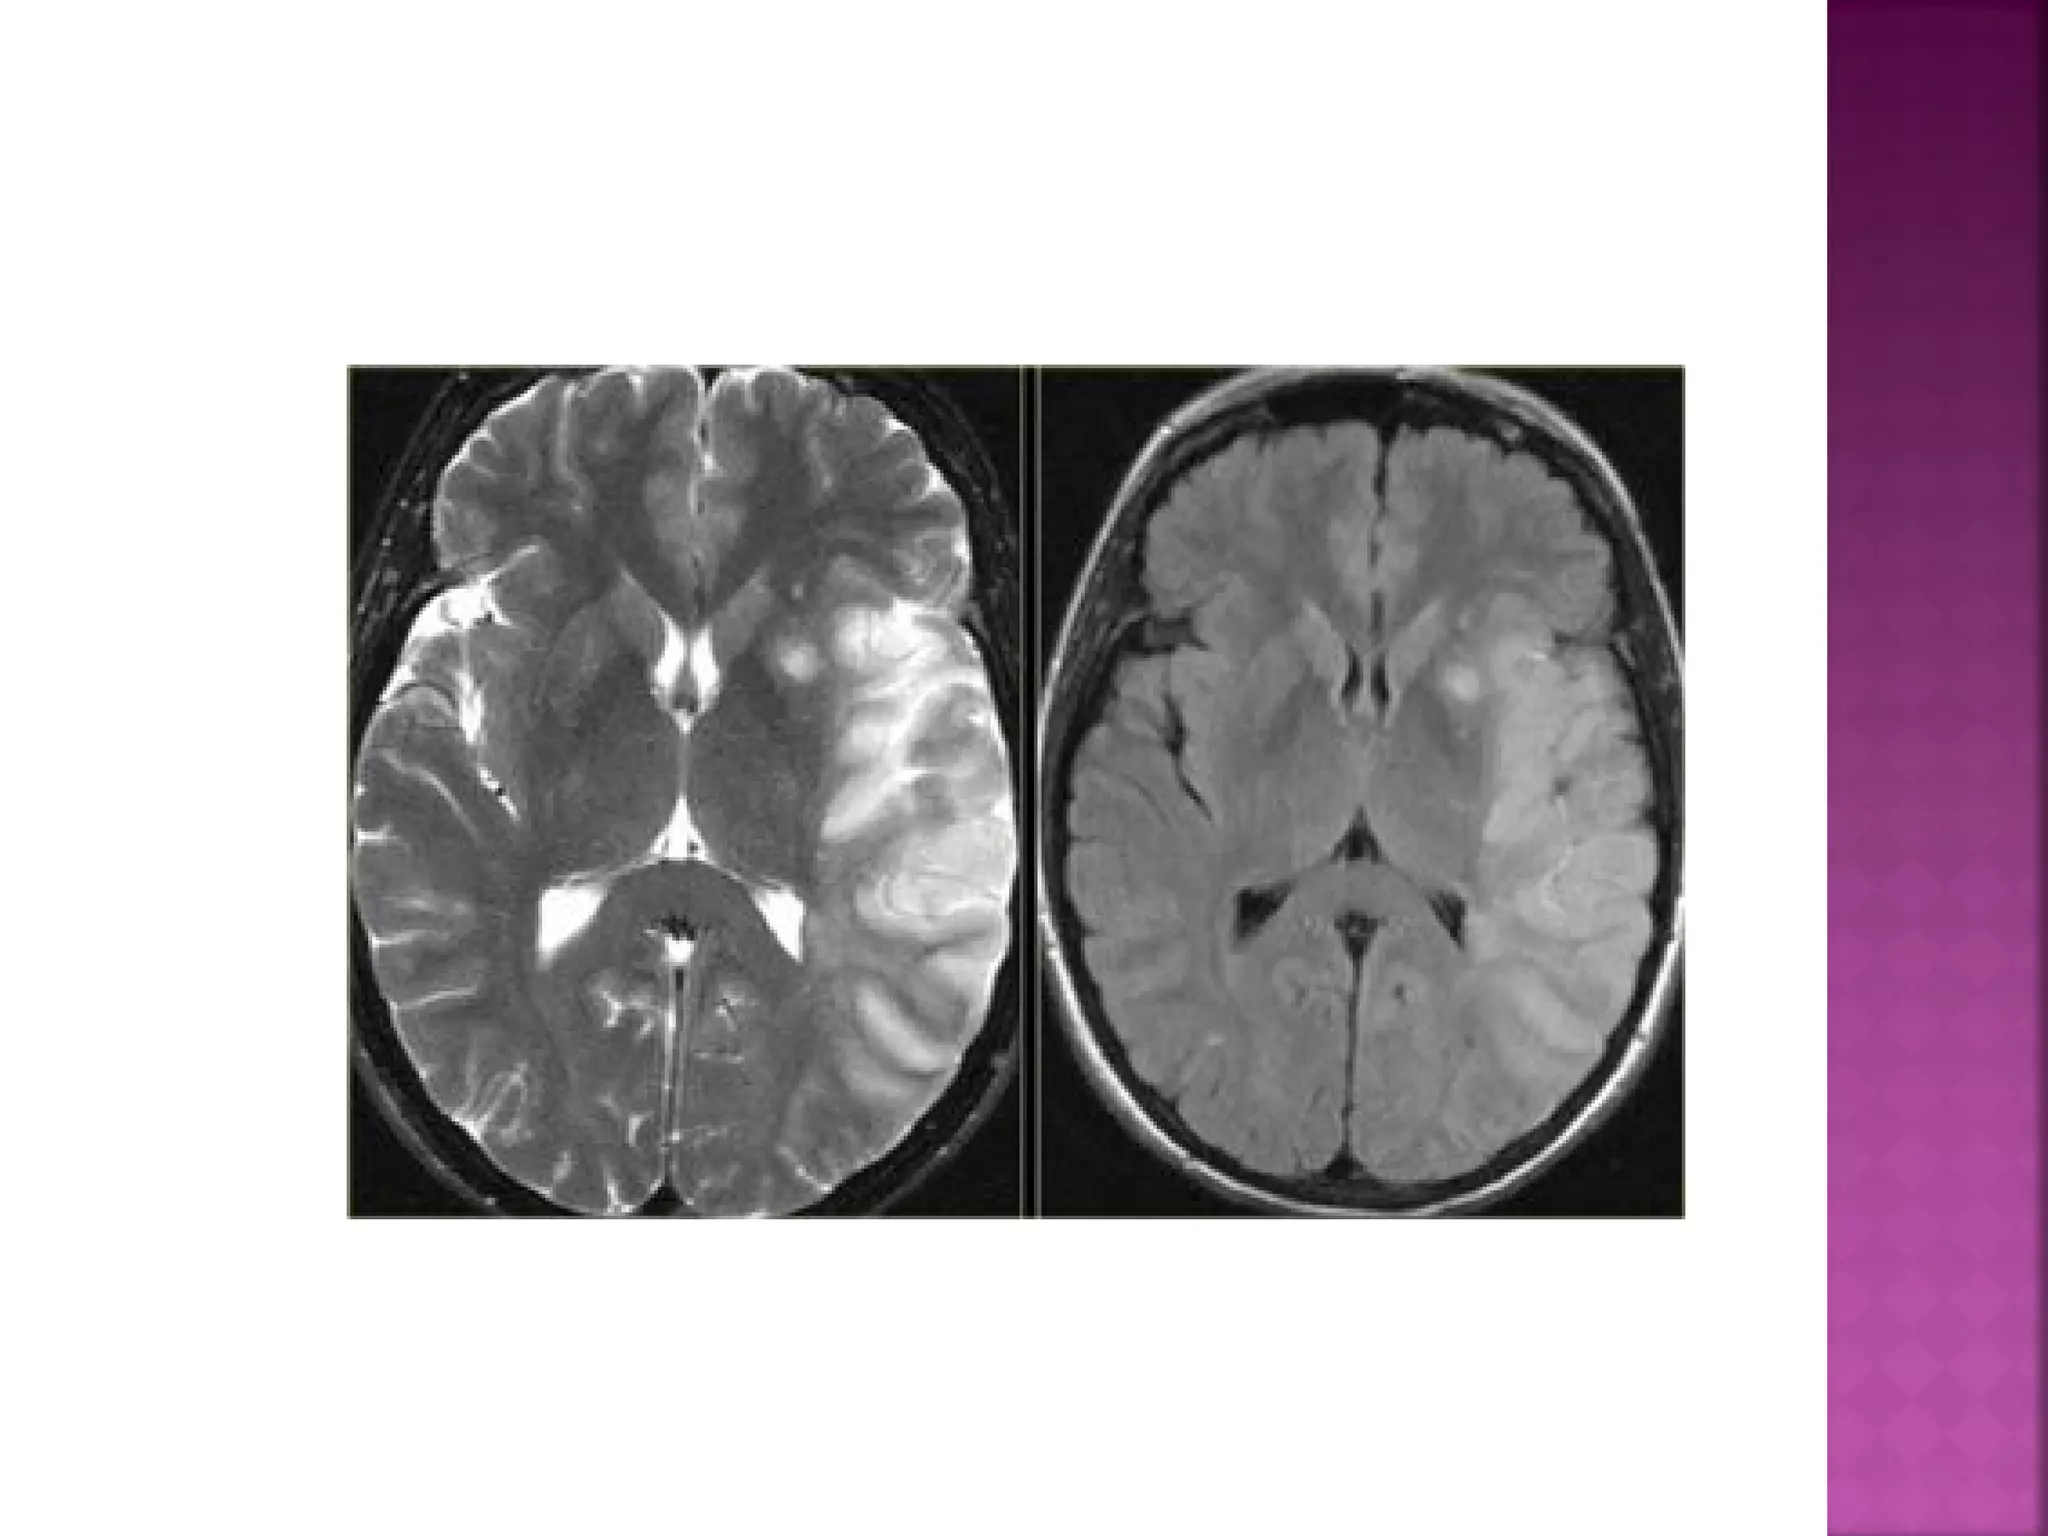

On T2WI and FLAIR infarction is seen as high

SI.

These sequences detect 80% of infarctions

before 24 hours.

They may be negative up to 2-4 hours postictus!

High signal on conventional MR-sequences is

comparable to hypodensity on CT.

It is the result of irreversible injury with cell

death.

So hyperintensity means BAD news: dead

brain.

In the acute phase T2WI will be normal, but

in time the infarcted area will become

hyperintense.

The hyperintensity on T2WI reaches its

maximum between 7 and 30 days. After this

it starts to fade